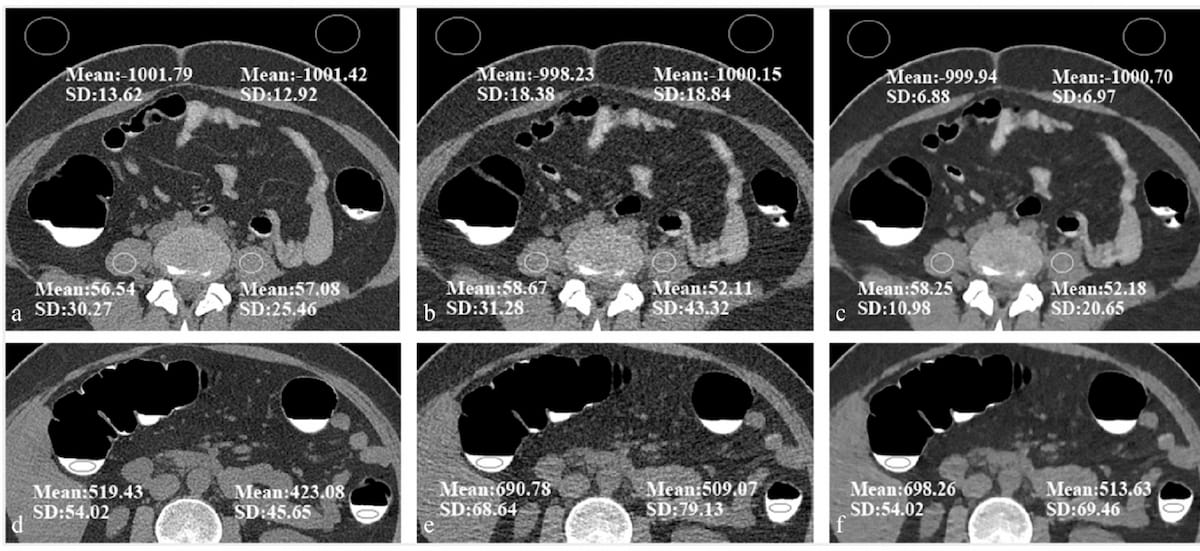

Reportedly offering improved delineation of pulmonary structures and greater accuracy with computed tomography (CT) values of pulmonary tissue, the artificial intelligence (AI)-powered LungQ 3.0.0. may facilitate enhanced precision and efficiency with interventional procedures such as lung volume reduction and ablation procedures.